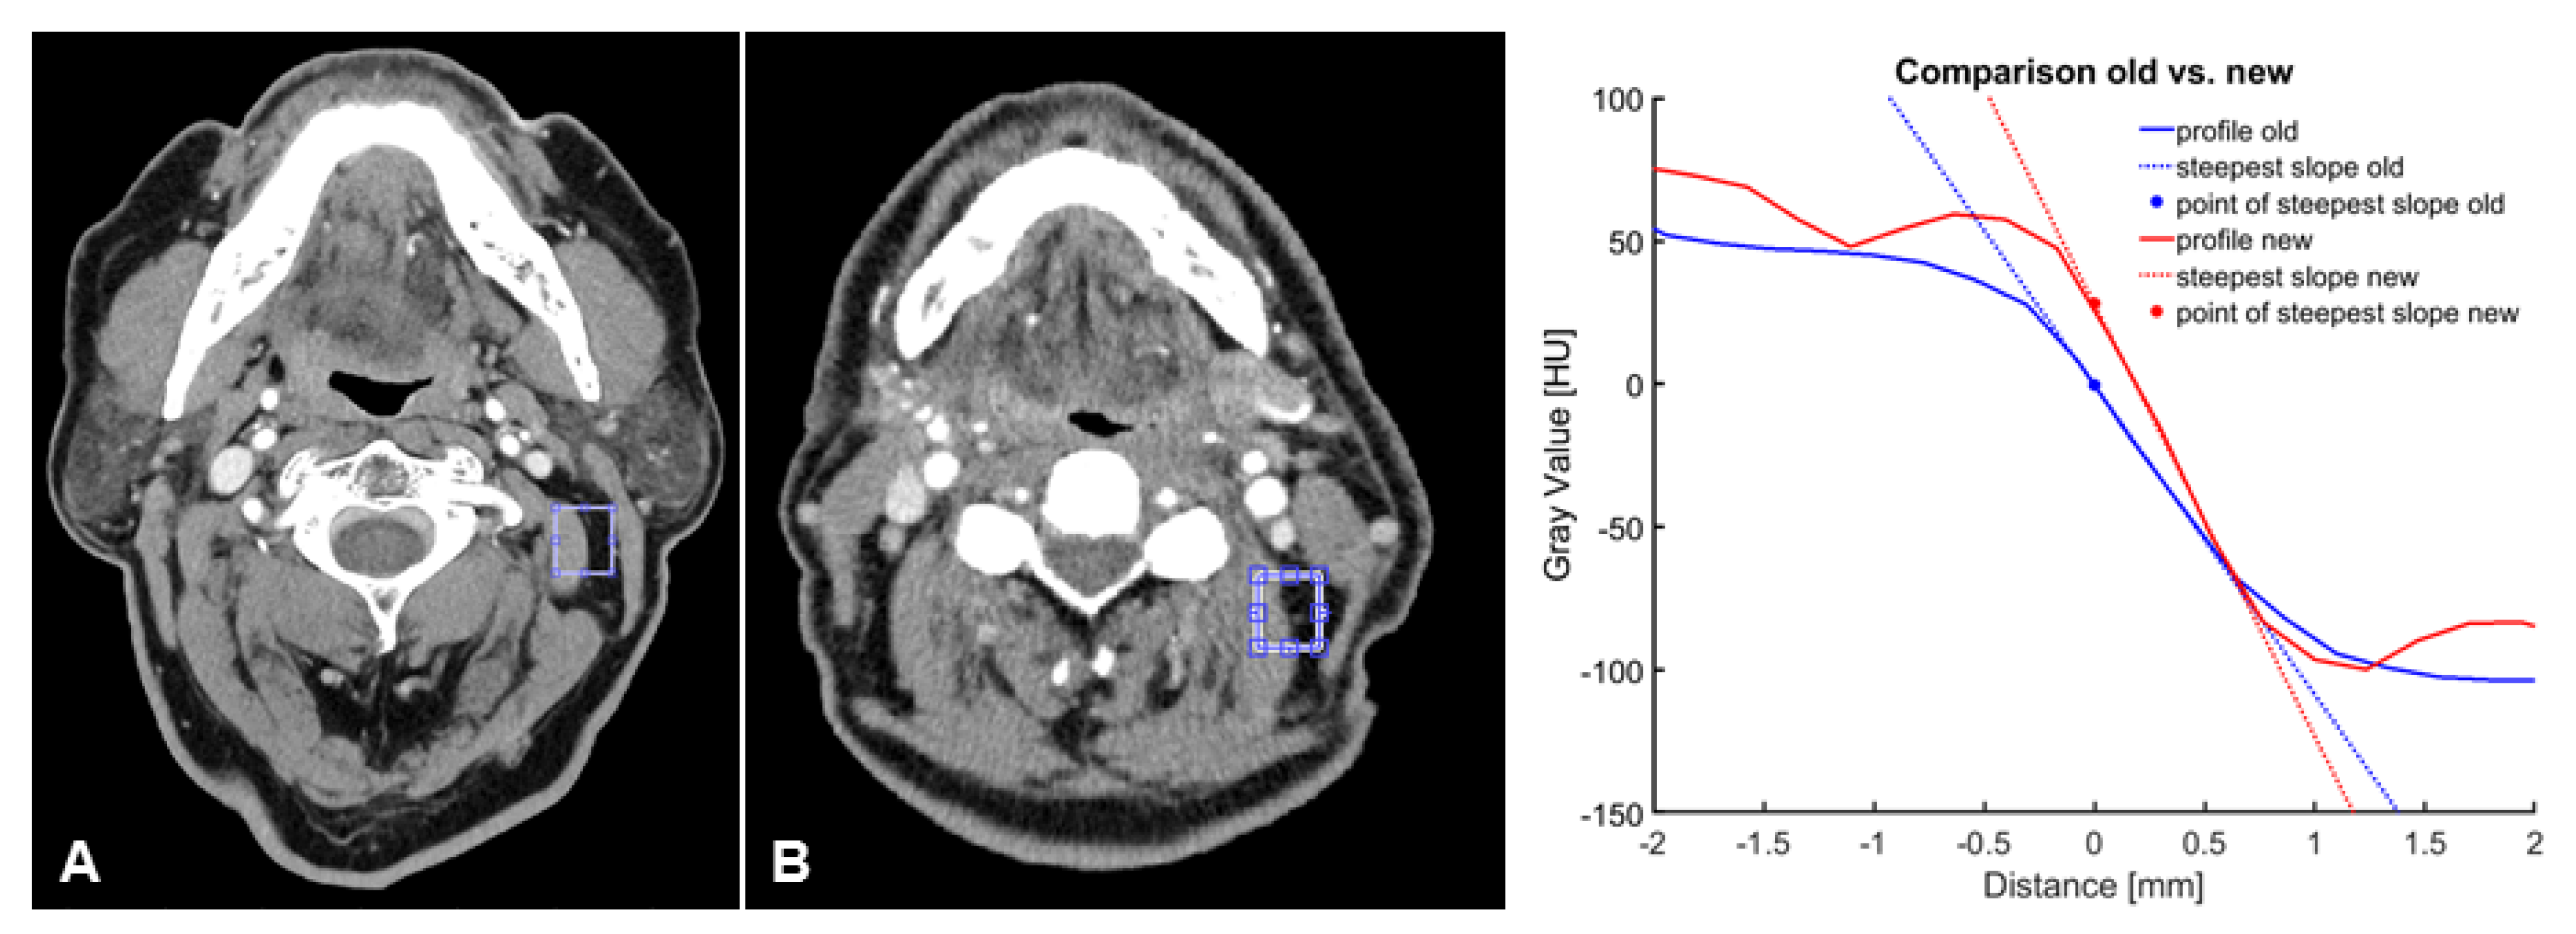

3.3. Objective Image Quality

| SNR | 10.8 [10.2–11.3] | 8.8 [7.9–9.6] | <0.000 |

| Steepest slope [HU/mm] | −168.4 [−(177.8–159.4)] | −94.5 [−(100.1–89.0)] | <0.000 |

| Distance [mm] within the IQR | −0.56 [−(0.5–0.58)] | −0.97 [−(1.02–0.908)] | <0.000 |

| CNR | 26.1 [24.2–26.0] | 22.9 [20.9–24.9] | <0.025 |